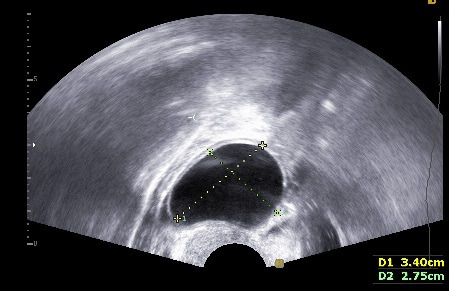

아래는 임신을 준비하는 여성들의 초음파 검사에서 관찰되는 영상입니다.

자궁근종이 있는지, 자궁 용종이 있는지, 난소에 혹이 있는지 확인할 수 있는 간편하면서도 정확도가 높은 검사입니다. 비용은 병원마다 천차만별이오니 꼭 미리 확인하고 가시기 바랍니다. 자궁근종, 자궁 용종, 난소에 자궁내막종의 여부에 따라 난임에 대한 접근방법이 바뀔 수 있어 필수적으로 시행하는 검사입니다.

초음파는 일종의 음파 (Sound wave)이며, 우리가 들을 수 있는 주파수 20Hz~20,000Hz를 넘어선 초월한 음파 입니다. 초음파의 경우 X-ray이나 CT와 달리 방사선 피폭이 없어서 태아를 관찰하기에 용이합니다.

여성 생식기를 보게 되며, 보는 방법에는 질식 초음파와 복식 초음파, 음순을 이용한 초음파 방법이 있습니다만, 가장 많이 이용하는 방법은 복식 초음파(Transabdominal USG)와 질식 초음파(Transvaginal USG)입니다. 쉽게 설명하면, 산모의 태아를 보듯 배를 통해서 보면 복식 초음파이고, 질(vagina), 아기가 나오는 길(산도)을 통해서 보게 되면 질식 초음파입니다.

임신하지 않은 여성이나 10~12주 이전 산모의 경우에는 태아가 작아서 질식 초음파를 이용해서 태아를 관찰하는 경우가 많습니다. 그리고 20주 이후에도 자궁경부를 확인하기 위해서 질식 초음파를 관찰할 때가 있습니다.

일반 여성 환자의 경우, 복부 초음파로 검사를 시행할 수도 있지만, 하복부 지방으로 인해서 복식 초음파가 쉽지 않을 때가 많고, 질식 초음파가 훨씬 선명하기에 질식 초음파를 사용하게 됩니다.